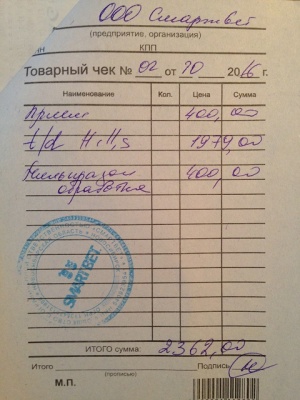

– прием дерматолога, врач Аверьянова Александра Михайловна, клиника АС Вет (400 руб.), вет диета Hills t/d для снятия налета с зубов (1979 руб.), Милпразон (антигельминтный препарат) 400 руб. (скидка на сумму чека 15%) (чек 3, копия чека 3, лист назначений – документ 3) – 2362 руб.

– прием дерматолога, врач Аверьянова Александра Михайловна, клиника АС Вет (400 руб.), вет диета Hills t/d для снятия налета с зубов (1979 руб.), Милпразон (антигельминтный препарат) 400 руб. (скидка на сумму чека 15%) (чек 3, копия чека 3, лист назначений – документ 3) – 2362 руб.